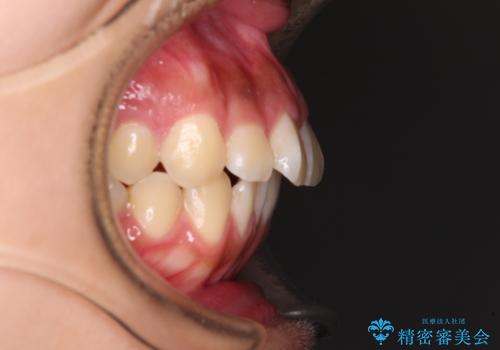

- 口元から飛び出てしまう前歯を気にして来院された患者様です。

上下前歯が嘴のように前方に突出しており、唇が閉じにくい状態であったため、上下左右の第一小臼歯4本を抜歯して、口元の突出感を改善することとしました。